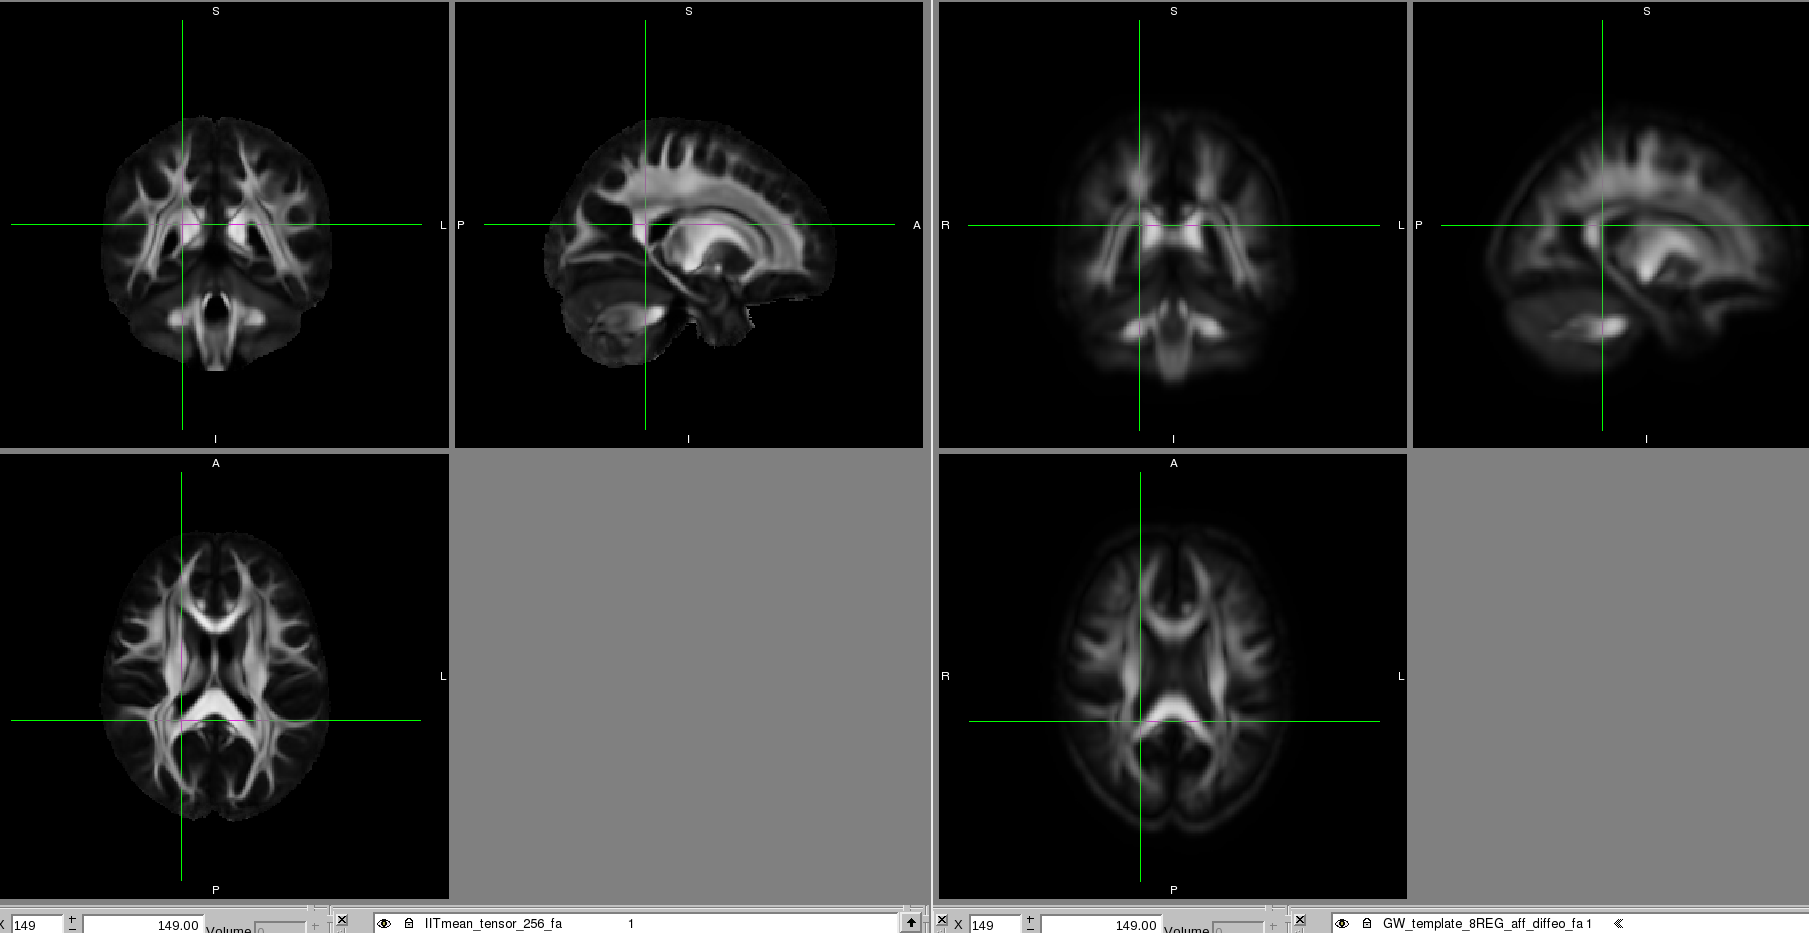

I've also been trying to alter the regularisation parameters for

the diffeomorphic step which seems to have improved it in that it

looks more normal. Please find attached a screen shot of the IIT

atlas (left) and the group wise deformably aligned using

regularisation parameters 200 times the weaker ones provided.

There are still regions not well aligned with the IIT atlas and the image is quite blurry. We think this is because there is quite a lot of atrophy in the brains, particularly in the caudate as the are huntington's disease patients, and the ventricles are enlarged.

I'd be interested in your opinion on this template and whether you know of ways to factor in brain atrophy when registering into the IIT standard space?